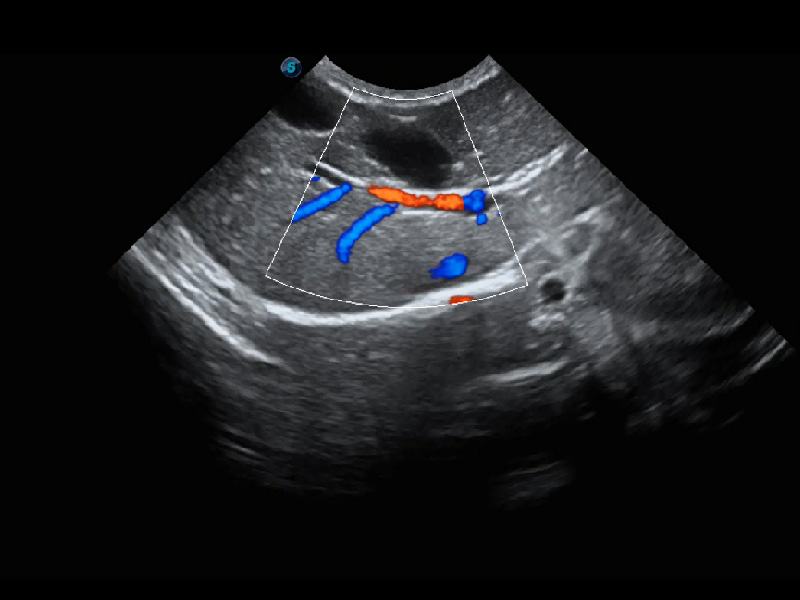

ProPet 60 作为一款高端台式动物超声设备,为动物医生的日常诊断提供了一系列贴合动物临床需求、解决临床实际问题的高级成像功能。凭借全系列高清探头,满足医生对腹部、心脏、生殖、浅表、肌骨等成像的所有需求,切实帮助您提升检查效率,提高诊断信心。

动物是人类最亲密的朋友和最值得信赖的伙伴。1xBET也一直致力于探索动物专用的超声影像解决方案。 全新推出的ProPet系列,是1xBET在动物超声影像智能化、专业化、精准化的一次跨越式革新。动物不能用言语来表述自己的不适,通过超声影像,ProPet系列搭建了动物医生与不同物种沟通的“桥梁”,为动物医生注入了“治愈之力”。